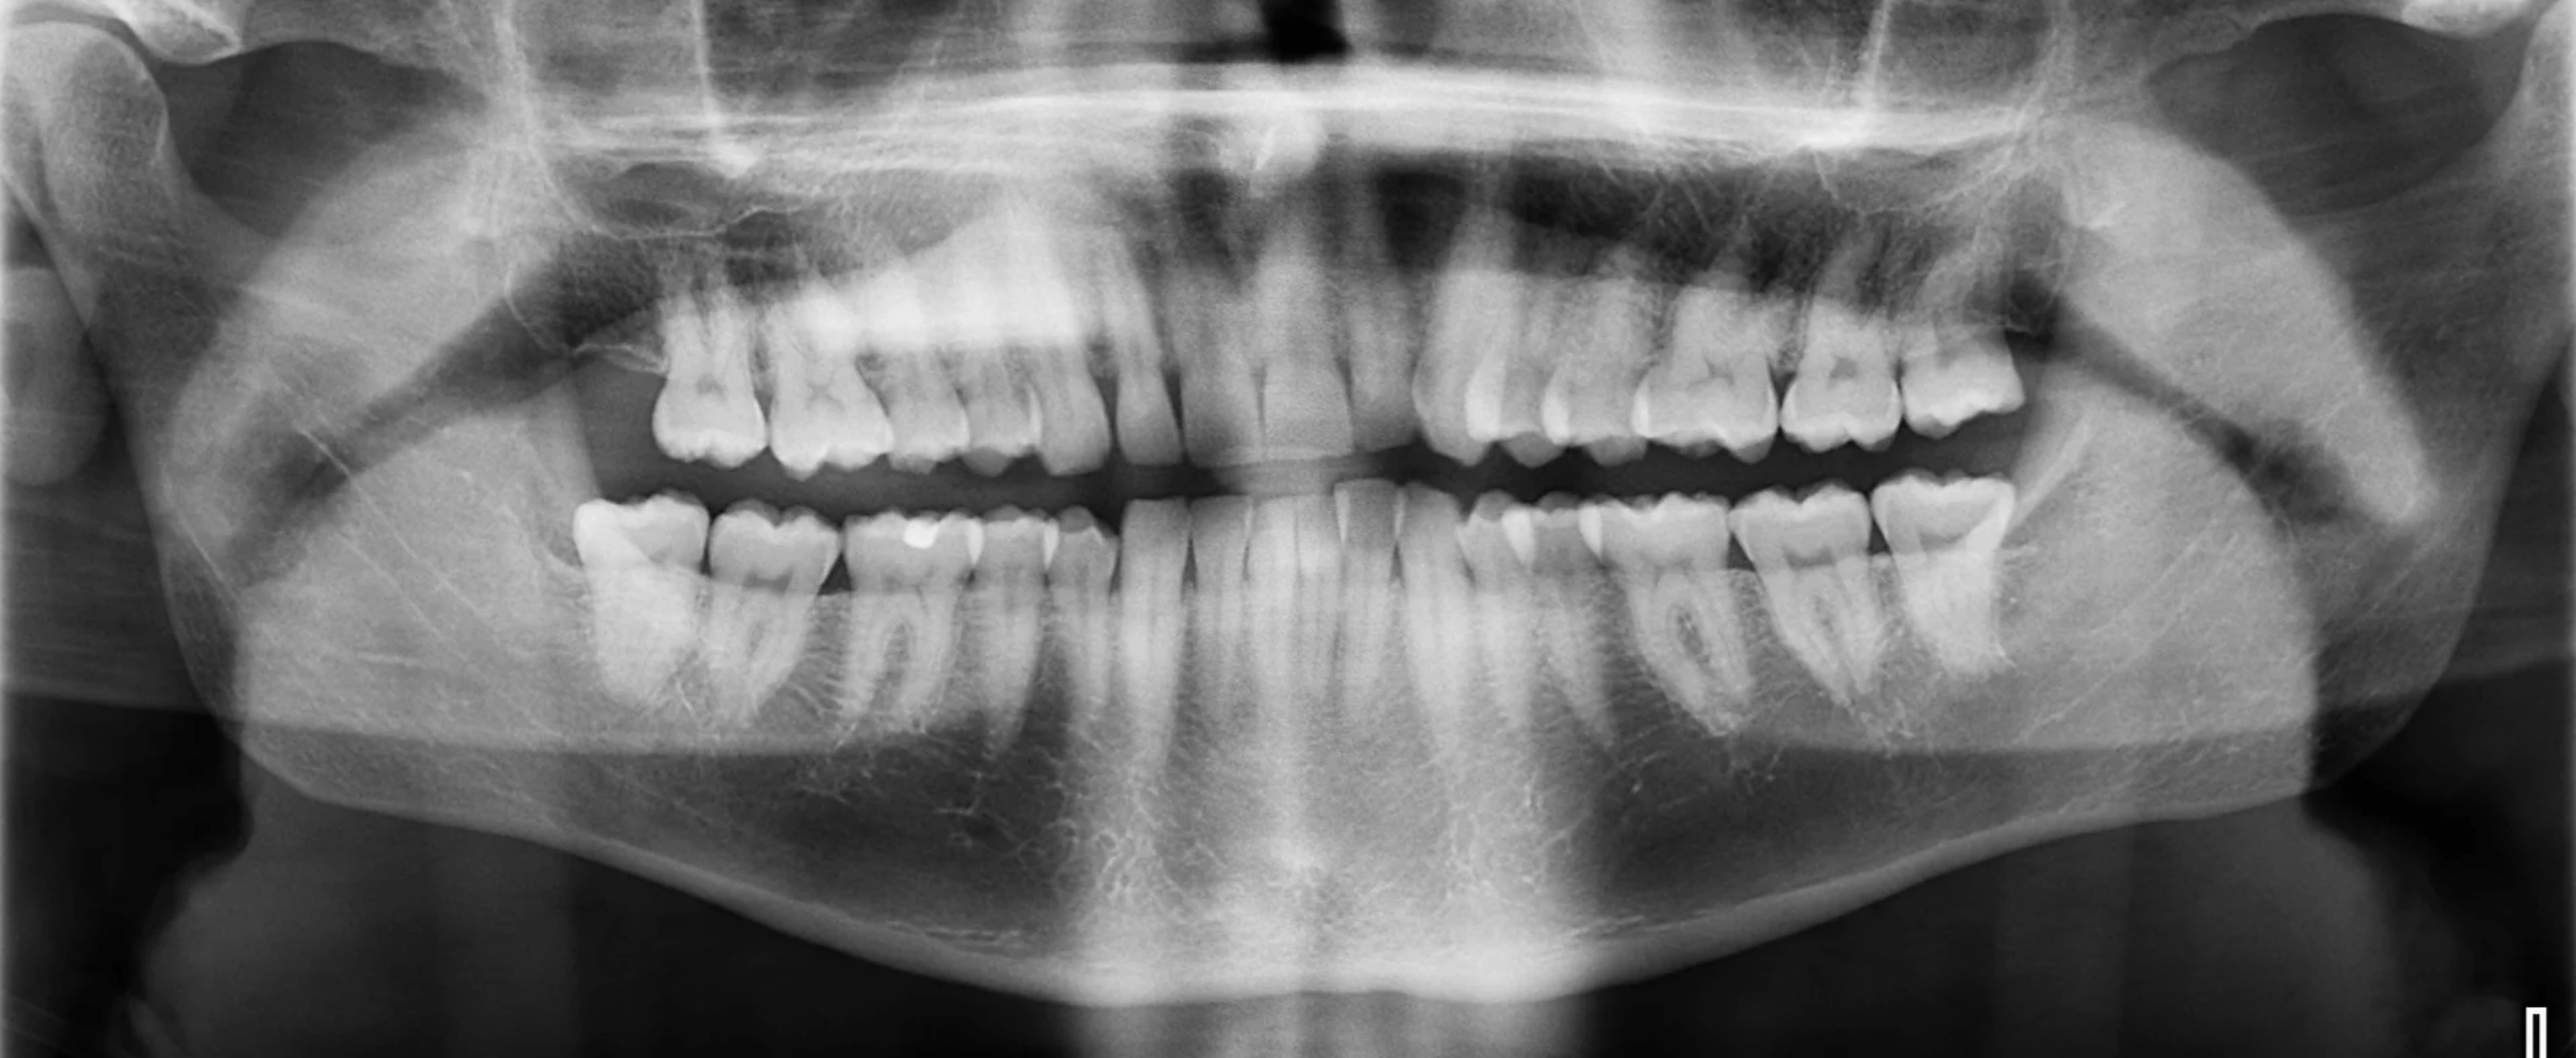

Before and After eMax Veneer Treatment